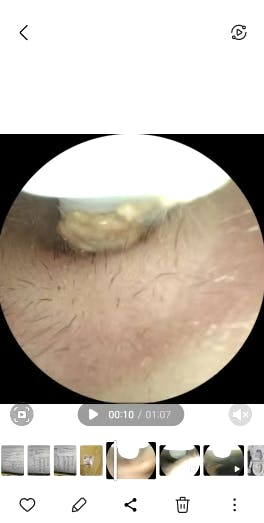

Ich habe eine starke Ohrenschmalzproduktion und es entstehen regelmäßig Propfen, die in der Vergangenheit regelmäßig vom Ohrenarzt entfernt werden mussten.

Mit diesel Gerät kann ich selbst in regelmäßigen Abständen das Ohr vom gröbsten Ohrenschmalz befreien. Mit diesem Gerät tut es überhaupt nicht weh, die Aufnahmen der Kamera sind sehr gut. Mit etwas Geduld, Übung und Vorsicht kann man das Ohr wirklich sehr gut reinigen, ohne es zu verletzen. Ich kann das Produkt ohne Vorbehalte weiterempfehlen und würde es wieder kaufen.

Habe das Gerät direkt getestet als es da war.

Die Kamera Auflösung ist perfekt und man kann alles erkennen.